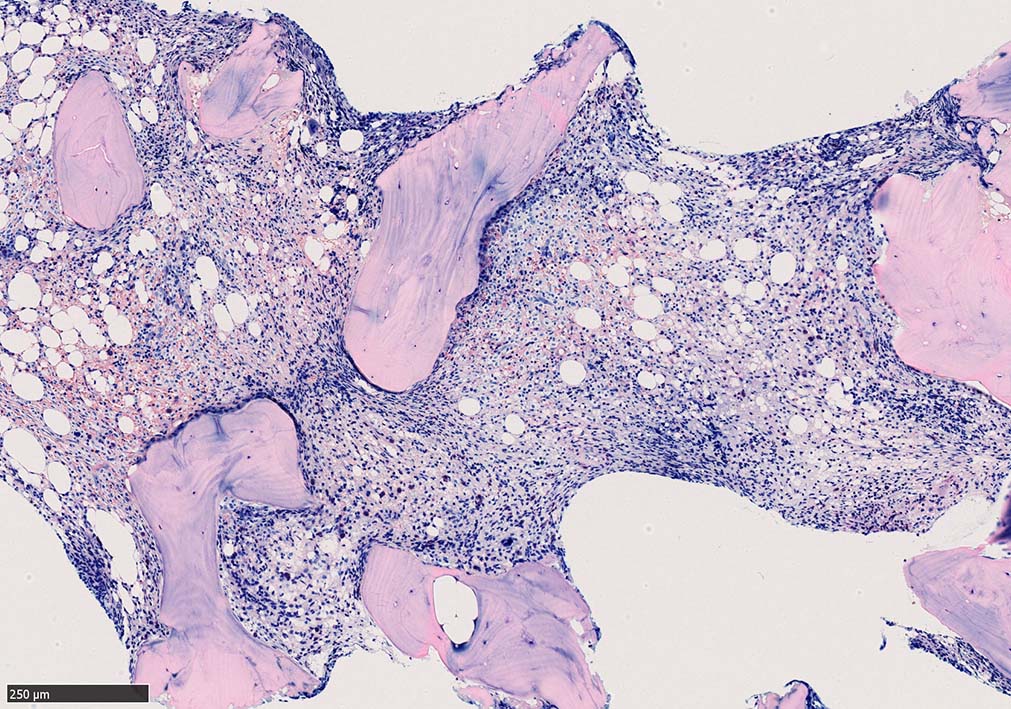

骨髄生検

bone marrow trephine biopsy: dry tapのため骨髄生検が行われる. cellularityは40-80%とhypercellular marrow. 流れのある細胞配列は線維化を疑わせる.

Ag染色では, 疎な弾性線維が増生し,増殖細胞を小胞巣状に分画するいわゆる「lymphomatoid pattern」を呈する. 本例では, Mgkに異形成所見がある.